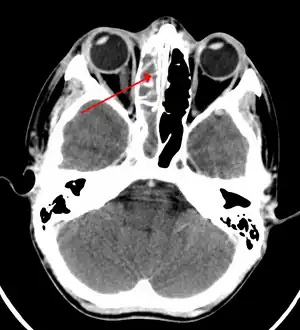

| A CT scan showing sinusitis of the ethmoid sinus | |

For sinusitis lasting more than 12 weeks, a CT scan is recommended.[54] On a CT scan, acute sinus secretions have a radiodensity of 10 to 25 Hounsfield units (HU), but in a more chronic state they become more viscous, with a radiodensity of 30 to 60 HU.[56]